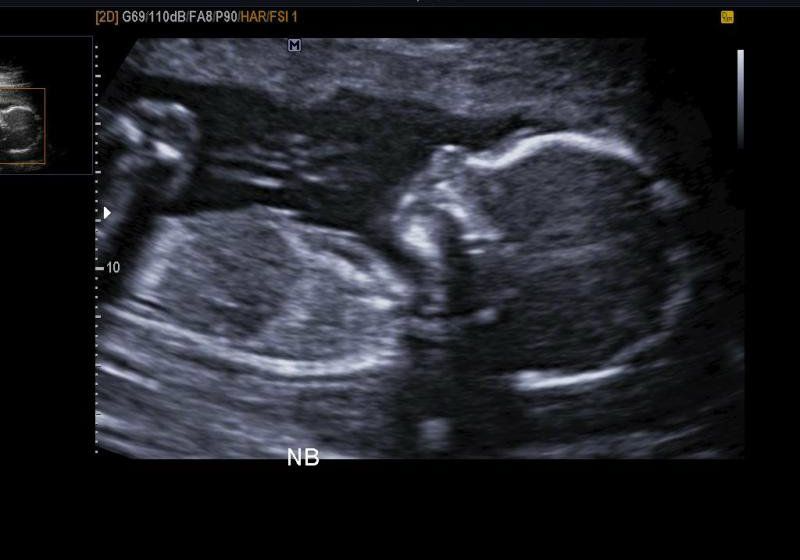

A bunch of new developments this week, but I'm going to start with our anatomy scan! Last Friday, the 20th Justin and I took the girls for my ultrasound. I had been worried that they wouldn't let the girls in the room, or that they'd act up so much that it would suck, but neither really happened so it was a good appointment! I can't say the girls were angels, they cried for me to pick them up when they saw I was laying on the table, but the technician was awesome and let me hold the girls on the table and told me that if I thought they were bothering here at all that I didn't need to worry because she has kids too and knows exactly how it is. She thought they were the cutest things ever, and she was really nice during the ultrasound. Bitty was a little quiet, kinda sleepy, he did move and twist a little bit but he wasn't going crazy or anything. She wasn't able to get all of his measurements because he was so sleepy so I have to go back in 4 weeks for another follow up ultrasound, not that I mind!

And if you didn't notice the pronouns I was using in that last paragraph, yes Bitty Bean is a BOY! We're so excited to bring a little boy into our family and I can't wait to see how much like daddy he looks like! He's going to be the cutest little guy in the world if he's anything like his beautiful sisters, and I get happy and excited every day thinking about meeting him! I'm trying not to be impatient but it's hard!

Size of baby - An heirloom tomato apparently. At the ultrasound he was approximately 9oz, and according to websites he should be about 10" or so. It's so weird that you can literally feel someone so small!